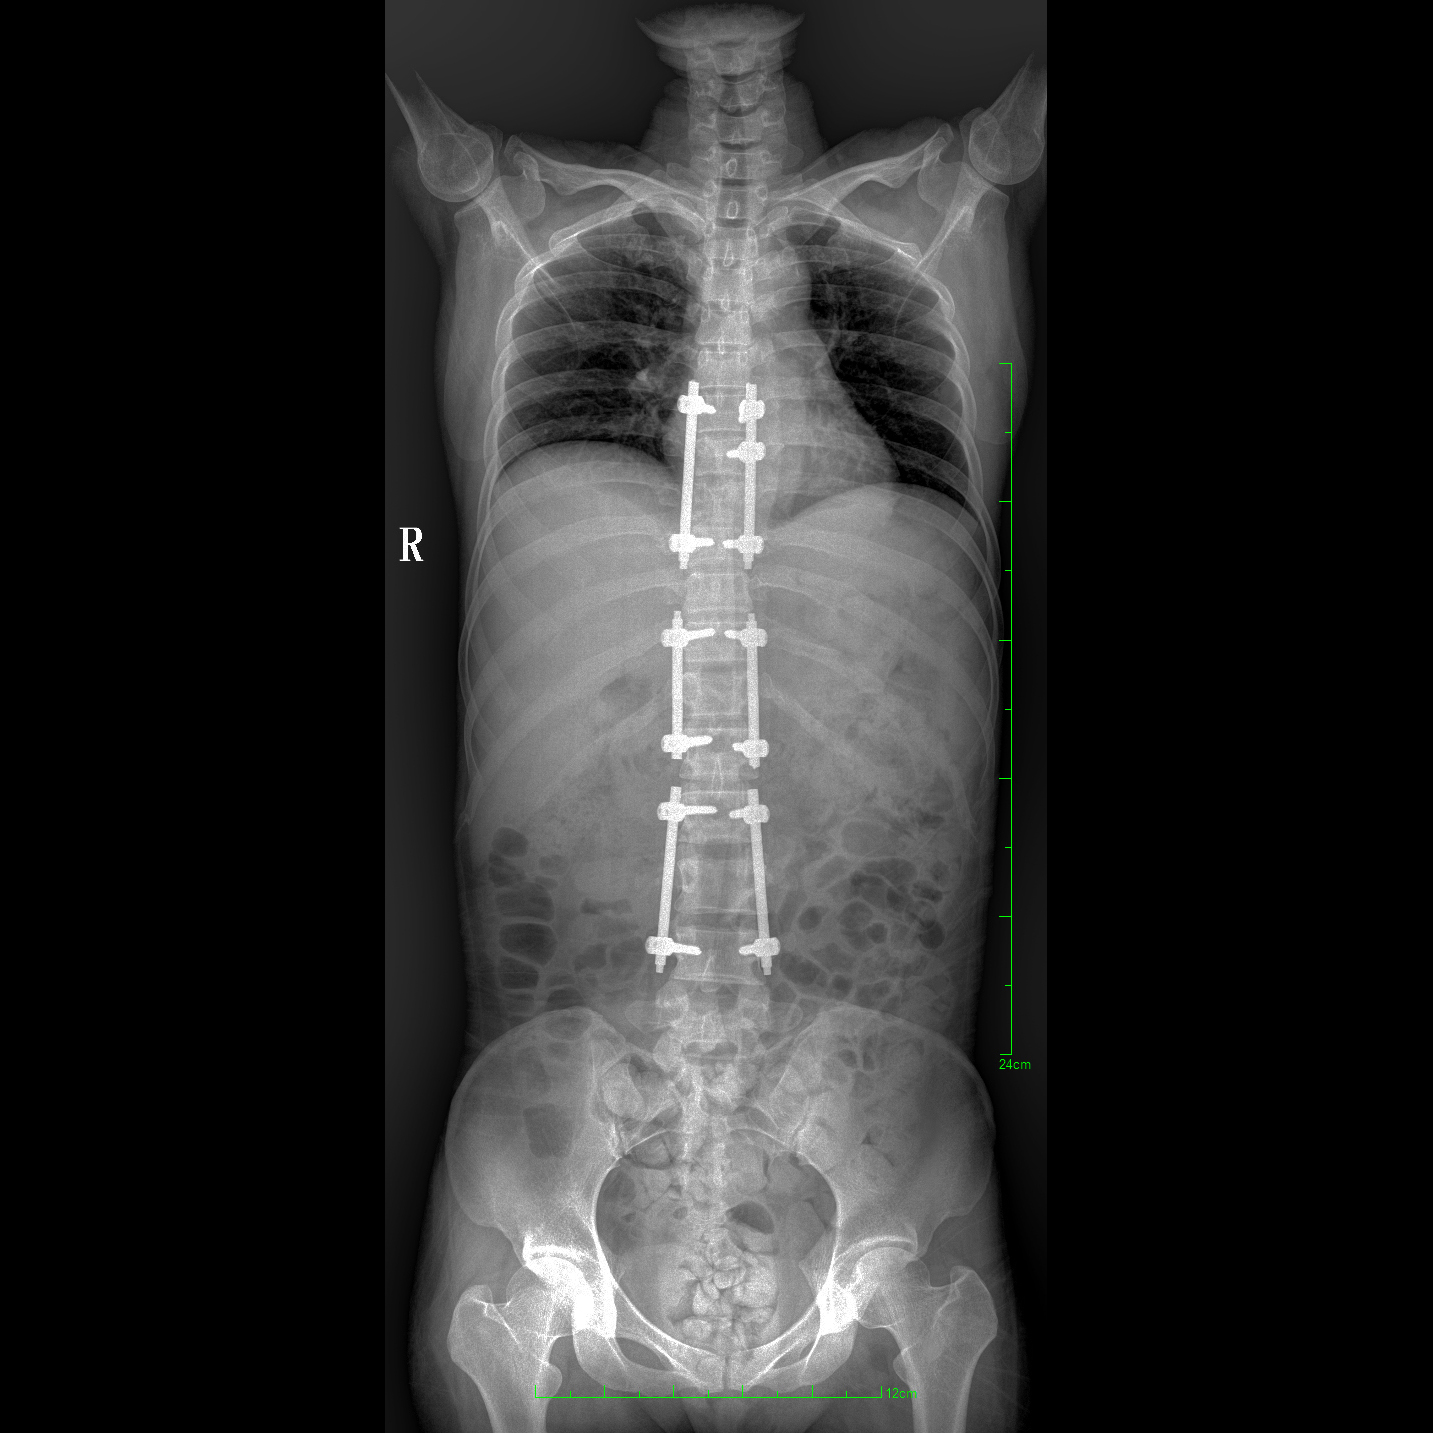

支持全脊柱攝影、雙下肢攝影、脊髓造影、復雜創(chuàng)傷、人工關(guān)節(jié)置換、關(guān)節(jié)損傷的修復重建等大視野臨床應用

17"*34"有效視野,一次成像不拼接。相較于多張攝影再軟件拼接的DR設備,PLX8600解決了拼接圖像存在密度不均勻,拼接處圖像配準和放大效應等問題,給臨床帶來了大視野影像解決方案,可一次性覆蓋全脊柱或雙下肢影像。